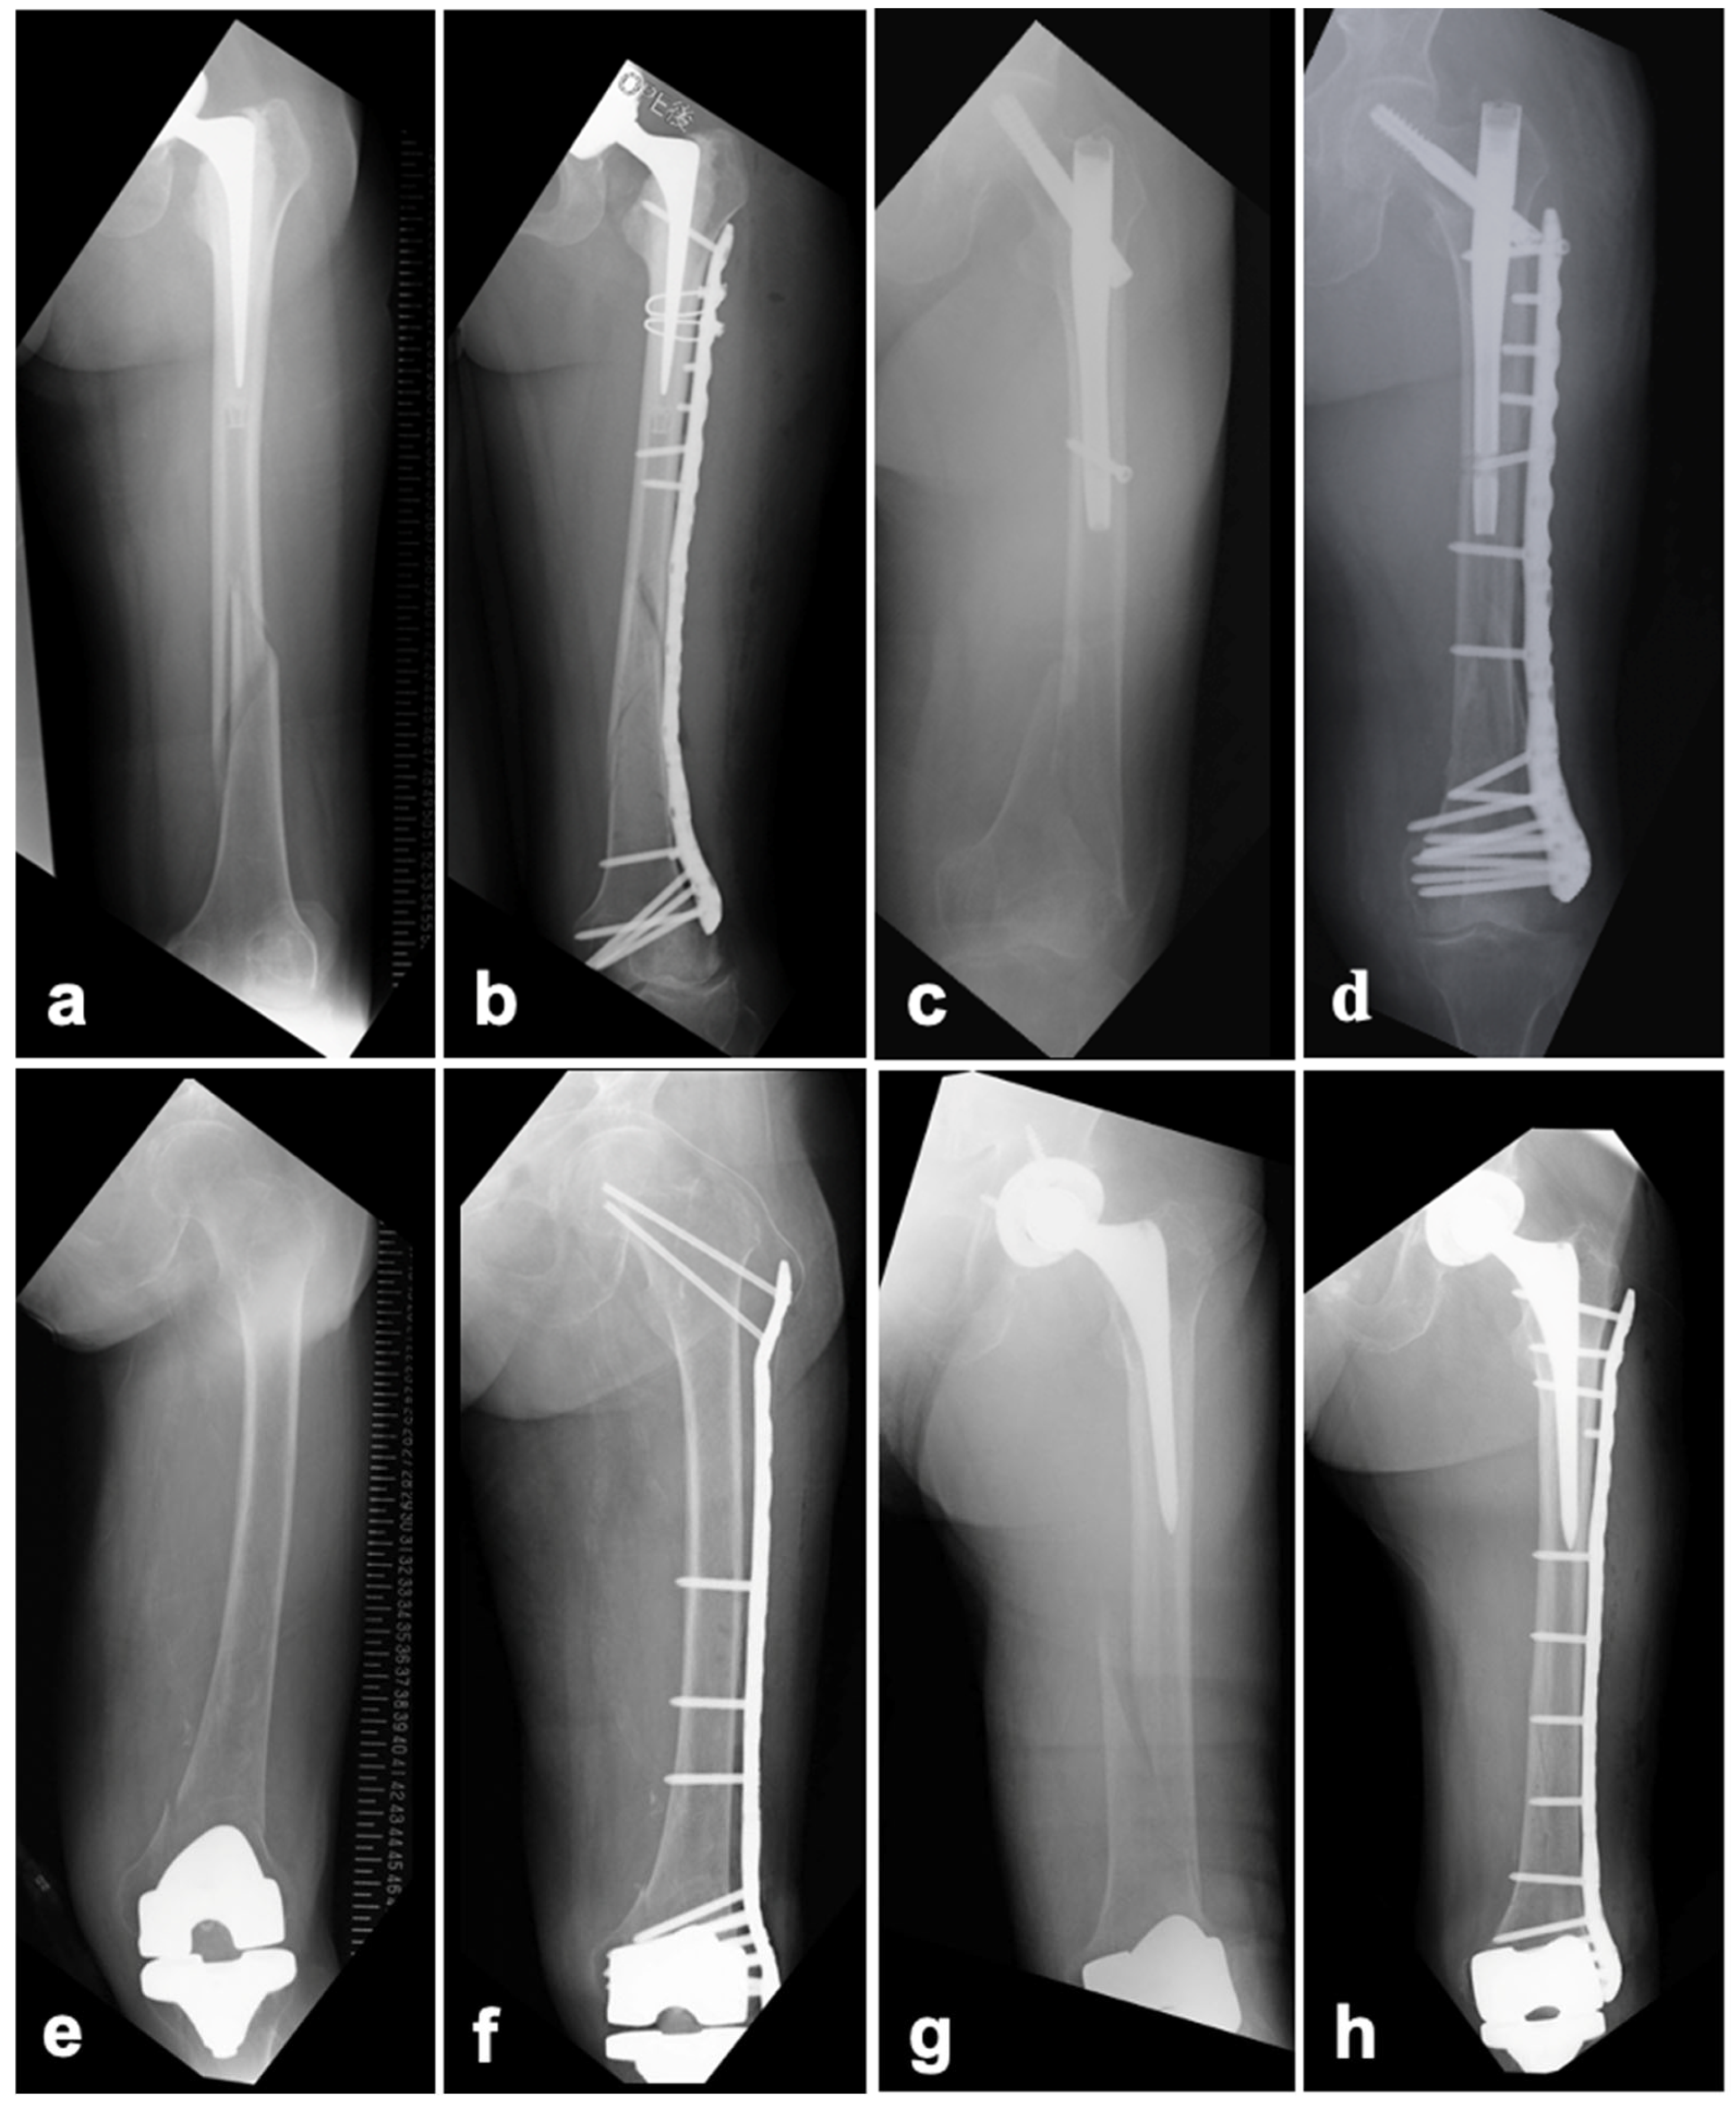

2.3.1. BHA/THA

2.3.2. SFN

2.3.3. TKA

3. Results